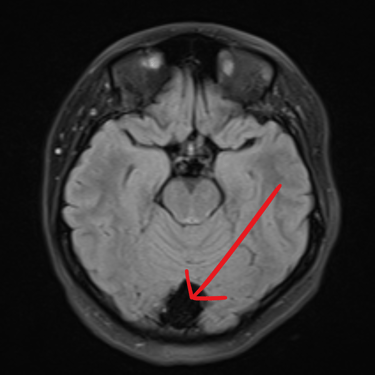

El quiste aracnoideo suboccipital es una lesión benigna de origen congénito, formada por una acumulación de líquido cefalorraquídeo entre las membranas aracnoideas. Aunque en muchos casos puede ser asintomático y detectarse de manera incidental, también puede producir cefalea, mareos, alteraciones del equilibrio o compresión del cerebelo y tronco encefálico. La resonancia magnética (RMN) es el estudio de elección, ya que permite definir la localización, tamaño y sus efectos sobre estructuras adyacentes. Este diagnóstico es clave para establecer la conducta terapéutica, que puede variar entre seguimiento clínico-radiológico o tratamiento quirúrgico en casos sintomáticos o de crecimiento progresivo.